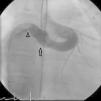

Nine months after the second intervention, coronary angiography was repeated. No fistulous flow was detected, the fistula being occluded 2 cm before the emergence of the Cx artery (Figure 4). LAD and Cx artery flows were normal. Following the second procedure the patient remains asymptomatic and well. Antiplatelet therapy with aspirin was continued.